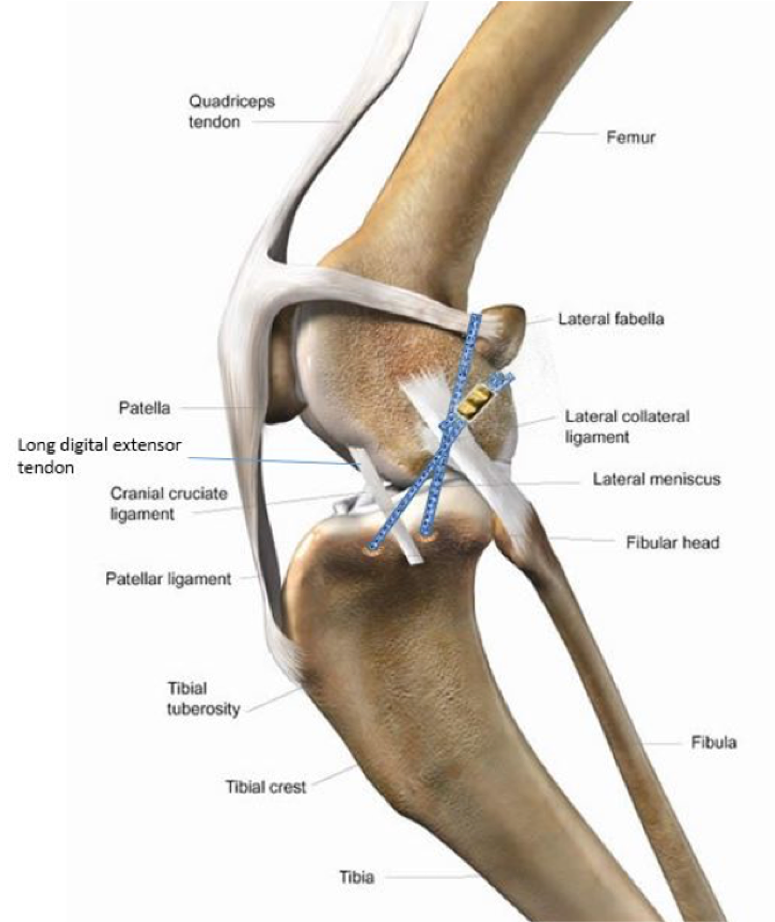

Understanding the Role of the ACL

The ACL plays a crucial role in stabilizing the knee joint by preventing the tibia (shin bone) from moving forward relative to the femur (thigh bone). It also limits rotational forces, preventing internal rotation of the knee. When the ACL is damaged, the knee becomes unstable, leading to pain, swelling, and secondary injuries such as:

Extracapsular Stabilization

This technique and its variants involve anchoring a synthetic suture-like material outside the joint capsule to stabilize the knee. By attaching this material to specific biomechanical points on the femur and tibia, it effectively mimics the ACL’s function from outside the joint. This method is particularly suitable for smaller dogs with mild tibial plateau angles, as their lower body weight and reduced joint stress make the procedure more effective and less prone to complications. While cost-effective, it is best suited for small dogs (under 40 lbs) with mild tibial plateau angles. Larger dogs or those with steep TPAs may experience faster joint degeneration with this method, and it is therefore not recommended in these cases..